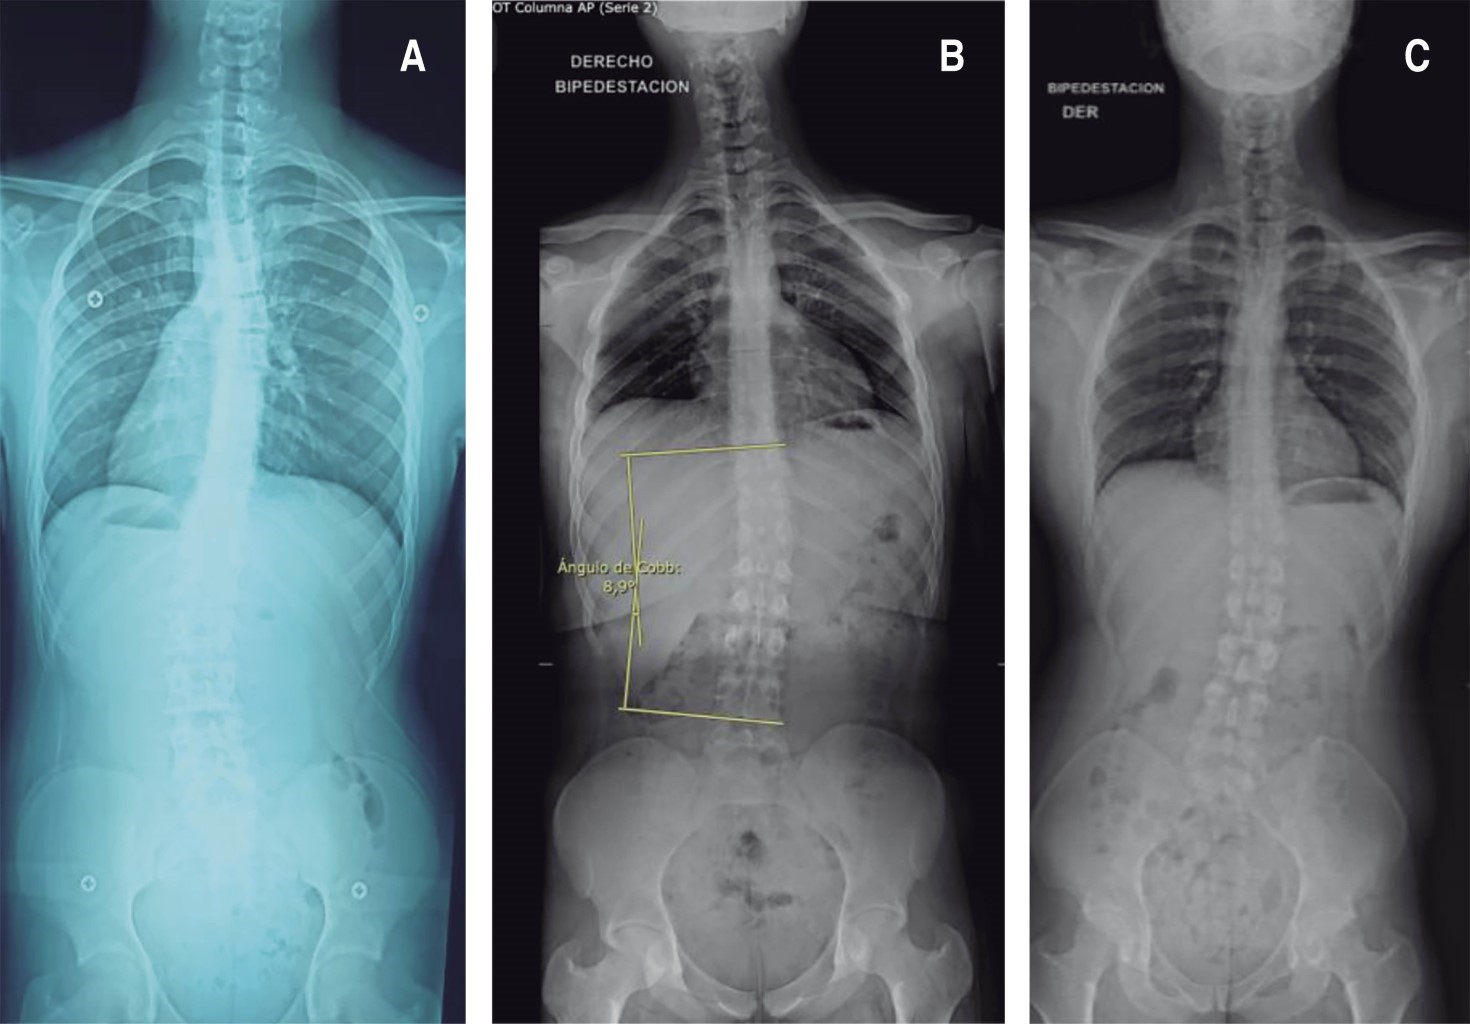

Caso 1. Paciente masculino de 12 años con estatura de 1.65 m y peso de 43 kg (índice de masa corporal [IMC] 15.79, bajo peso). Acude por dolor en columna dorsolumbar de 4-5 años de evolución, que se exacerba al estar acostado y al cargar objetos pesados. Presenta hipercifosis, con prueba de Adams negativa. Deambulación adecuada con capacidad de realizar prueba punta-talón. La exploración de miotomas y dermatomas se encuentra sin alteraciones, sin datos de neurotensión ni sacroilitis. No presenta datos de radiculopatía ni señales de alarma. Los estudios de resonancia magnética nuclear (RMN) y radiografías confirman el diagnóstico de enfermedad de Scheuermann, evidenciando afectación de 4-5 vértebras y una cifosis dorsal de 60 grados. Se indica tratamiento con corsé y seguimiento en seis meses con radiografía de control (Tablas 1 y 2; Figura 1).

Caso 3. Paciente masculino de 16 años con estatura de 1.86 m que acude por presentar joroba en espalda, sin dolor ni síntomas neurológicos asociados. Presenta tono, trofismo, fuerza, reflejos, sensibilidad y arcos de movimiento normales. Sin maniobras de neurotensión ni disfunción sacroilíaca. Las radiografías panorámicas muestran cifosis dorsal de 70°, escoliosis lumbar leve no mayor a 10°, acuñamiento vertebral dorsal y disminución del espacio discal dorsal. Risser 5 en pelvis, que indica bajo potencial de progresión. Se establece plan de seguimiento cada seis meses con rayos X panorámicos. Pronóstico favorable dado el bajo potencial de progresión (Tablas 1 y 2; Figura 2).

La deformidad cifótica es un hallazgo constante, pero con variaciones en su severidad, y frecuentemente se acompaña de escoliosis de grado variable. Se encontró una variabilidad significativa tanto en el plano sagital como coronal. En el plano sagital, la cifosis dorsal oscila entre 50° y 70°, presentándose los casos más severos en un adolescente de 16 años (70°) y en un adulto de 33 años (65°), mientras que los casos más leves se observaron en individuos más jóvenes. En el plano coronal, los pacientes presentan deformidades escolióticas con un espectro desde curvas leves (< 10°) hasta moderadas (30° torácica izquierda), con algunos casos que presentaron patrones de doble curva. Además, los cambios estructurales incluyen con frecuencia acuñamiento vertebral de 4-5 vértebras, con cambios discales más prominentes en adultos.